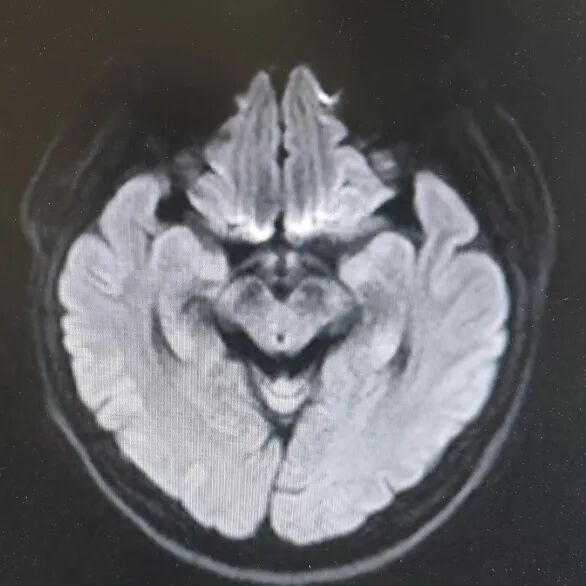

引言 生活中,很多人会突然出现“看东西重影”的情况,往往以为是眼睛疲劳或近视加深,并没有太当回事。然而,这背后可能隐藏着甲亢、脑梗、重症肌无力甚至肿瘤等十余种疾病的信号,是一个需要警惕的“隐形杀手”。 面对这类病因错综复杂的“复视”患者,市二院神经内二科赵智江主任带领团队,凭借丰富的临床经验和深厚的神经疾病诊疗功底,抽丝剥茧,多次成功揪出导致视物成双的“真凶”,为患者赢得了宝贵的治疗时机。 Part.01 复视背后,病因五花八门 神经内二科团队诊治了多位以“视物成双”为主诉的患者,其最终病因各异,充分体现了神经科疾病“同症异源”的复杂性。 以为是眼病,其实是甲亢 患者因复视就诊,经查双眼突出,影像检查发现控制眼球的肌肉异常肥厚。结合甲状腺功能检查,最终确诊为“甲亢性眼肌病”,其原因在甲状腺功能亢进的眼部表现。后经针对性纠正甲状腺功能,患者复视症状显著改善,眼外肌肥厚得到有效控制。 眼眶核磁 甲功结果 眼球状态 复视眼痛,原是痛性眼肌麻痹 患者右眼不仅看东西重影,还出现上睑下垂、眼痛等症状。团队排除其他可能后,诊断为痛性眼肌麻痹(Toloas-Hunt综合征),这是一种自身免疫性炎症。经治疗,患者眼睑下垂症状减轻,眼痛及复视基本消失,眼球运动范围显著恢复。 梅毒隐匿,损伤颅神经 患者因眼皮抬不起、眼球转动不灵并视物重影入院。常规血清检查发现梅毒抗体阳性,排除其它原因导致的复视,最终明确为“神经梅毒”侵蚀颅神经所致。确诊后立即给予驱梅治疗,效果明显,眼皮能抬起来了,重影消失了,眼球转动也灵活了。 糖尿病悄悄损伤神经 两位糖尿病患者,均以突发复视就诊。团队精准判断,发现分别是高血糖损伤了“动眼神经”和“外展神经”,属于糖尿病性单神经病变,表现为不同类型的复影(上下重影或水平重影)。明确诊断后,经严格控糖,辅以营养神经药物等综合对症治疗,患者病情好转,顺利出院。 脑梗“瞄准”不同区域 三位患者均因复视就诊,但伴随症状各异,有的行走不稳,有的走路右偏。赵智江主任团队通过精细的神经系统查体,精准定位于中脑的动眼神经核、桥脑的内侧纵束等。不同脑区梗死,复视的表现也完全不同。后通过溶栓药物、抗血小板药物、改善循环治疗等针对性治疗,辅以康复治疗,患者身体逐渐好转,出院时已无视物成双症状。 三位患者的核磁 典型信号——晨轻暮重 患者出现复视,伴言语不利、吞咽困难、饮水呛咳等症状。其中复视有个鲜明特点——早晨轻、傍晚重,疲劳后加重。经专项检查,确诊为“重症肌无力”(眼肌型)。这是一种神经肌肉接头疾病,免疫调节治疗可有效控制。经过一段时间的治疗,患者复视症状明显缓解,言语不清、吞咽困难症状得到显著改善。治疗前患者只能进食流食,治疗后可自主进食固体食物。 肿瘤病史者,需警惕转移 淋巴瘤患者在化疗期间出现复视和面瘫。团队通过脑脊液等深入检查,排除感染等因素,最终诊断为脑膜癌病。 嗜睡头晕,病因在营养 患者急性起病,表现为复视、头晕、嗜睡、走路不稳。团队结合其既往史和典型眼球活动障碍,迅速锁定病因——因维生素B1严重缺乏导致的“韦尼克脑病(Wernicke)”。补充维生素B1一周以后,患者复视症状改善、走路平稳、神志清楚,可独立行走。 Part.02 精准诊疗,揪出“元凶”是关键 赵智江主任指出:“复视只是一个临床症状,其背后可能是内分泌、炎症、代谢、脑血管、自身免疫、肿瘤等多种病因在神经系统上的投射,涉及学科广泛。” 市二院神经内二科团队通过详细追溯病史、进行一丝不苟的神经系统专科查体(尤其是眼球运动检查),初步判断病变可能位于动眼、滑车、外展神经的神经核团,神经及其所支配的肌肉、神经-肌肉接头等部位,然后精准选择并解读影像学、免疫学、生化及脑脊液等检查结果,最终整合信息,明确诊断,为患者制定出针对性的治疗方案。 市二院神经内二科在赵智江主任的带领下,始终致力于复杂疑难神经系统疾病的诊疗攻坚。科室凭借严谨的临床路径、对神经解剖与病理生理机制的深刻把握,以及精湛的诊疗技术,为众多罕见病与危重患者精准定位病因、制定个体化治疗方案,有效提升了救治成功率与患者长期生活质量。 提醒市民:如果突然出现视物重影,尤其是伴有眼皮下垂、眼球转动不灵、疼痛、头晕、行走不稳或其他神经系统症状时,切勿掉以轻心,应及时重视,这些症状有时可能与神经系统疾病相关。为了明确原因,获得更全面的评估,您可以考虑到神经内二科就诊,由专业医生进一步检查与诊断,以便尽早获得适合的照顾与治疗。 Part.03 人民医院 人民名医 赵智江 主任医师 副教授 ·葫芦岛市第二人民医院神经内二科主任 ·中国卒中学会高级会员 ·中国老年保健医学研究会老年脑血管病分会委员 ·北京神经内科学会脑小血管病学会委员 ·安徽医药杂志审稿专家 ·辽西神经疾病专科联盟理事 ·辽西认知功能障碍联盟理事 ·辽西神经免疫学会委员 ·葫芦岛市医学会神经病学分会委员 专业特色:以脑血管病为核心研究方向,擅长各类神经系统疾病的诊疗,尤其在脑血管病、帕金森综合征、头晕、头痛、癫痫、重症肌无力、多发性硬化等神经免疫性疾病以及其它神经系统疑难、危重疾病的诊疗方面积累了丰富的临床经验。 出诊时间:每周一、周四全天 咨询热线:0429-8010317